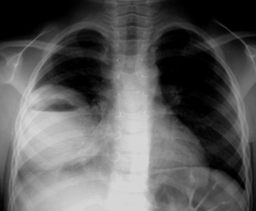

②肺膿腫:

起病急,有高熱、咳嗽、大量膿臭痰。

X線檢查可見局部濃密炎癥陰影,中有氣液平面。

影像:氣液平面